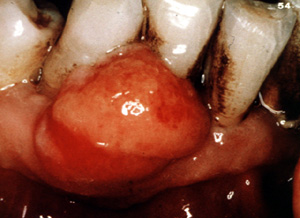

El término periférico es porque se originan en los tejidos blandos. Hay también un granuloma celulas gigantes "central" que se origina dentro del hueso y es más agresivo y destructivo en su conducta de crecimiento.

Esta imagen ilustra bien cómo estas lesiones pueden crecer sin tratamiento. El hueso subyacente puede ser reabsorbido.